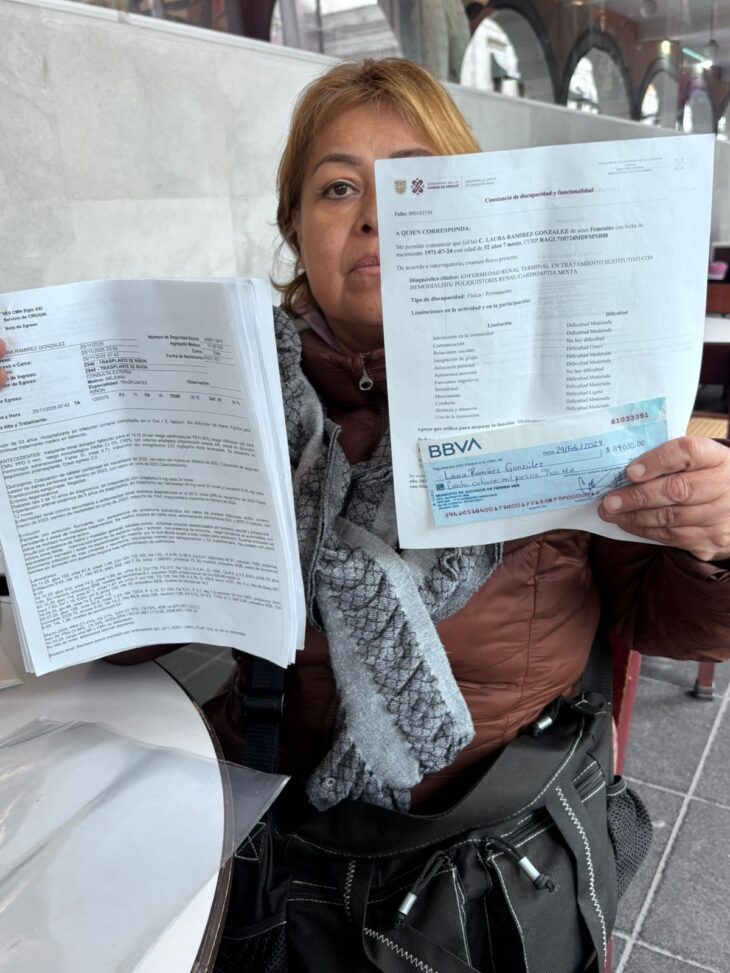

Cruz Cuevas se niega a pagar $114,000.00 por 24 ataúdes adquiridos por su comuna

• Proveedora denuncia que los féretros fueron entregados para ser entregados al ayuntamiento de Juchique de Ferrer por su familia, entregando cheques sin fondo. Irineo Pérez Melo.- Cruz Cuevas […]